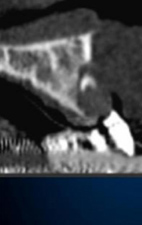

抜歯後CT 撮影 1

3D画像を構築する唇側の骨欠損が広範囲に及んでいる

理想的な位置に埋入すると骨が不足する

抜歯後CT 撮影 2

ブロック骨移植後CT

3D画像を構築する

理想的な位置にインプラントを埋入することができる